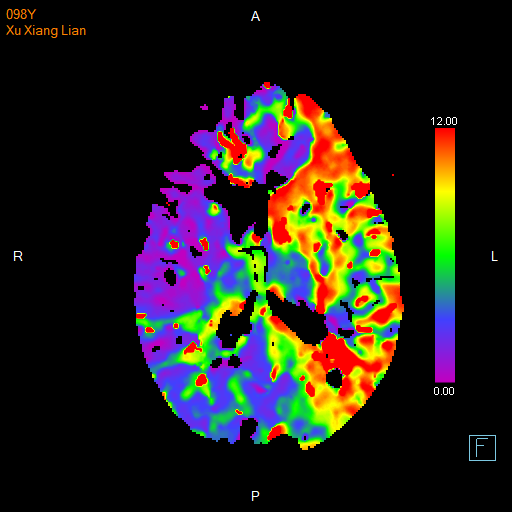

进一步的血管检查(CTA+CTP)发现了更严重的问题:王奶奶的左侧颈内动脉完全闭塞——这是脑梗中最凶险的类型之一,意味着大脑主要供血通道被切断,随时可能危及生命

颅脑 CTP